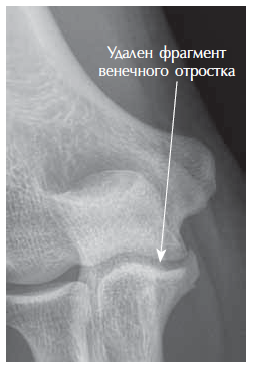

Given that the patient had engaged in sports and there was marked pain syndrome, ectomy of a fragment of the coronoid process was performed (Figure 4).

Fig. 4. Anterior–posterior radiograph of the left elbow joint after the surgery